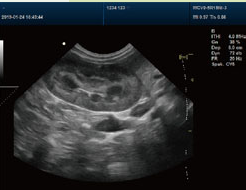

肾结石超声检查 |

肾结石超声检查是一种常用、无创的影像学手段,主要用于检测结石位置、大小、数量及是否引发肾积水。超声通过声波成像,适用于初步筛查和随访,但可能因肠道气体或结石过小出现漏诊,需结合CT等进一步检查。 一、超声检查的优势 1、无辐射:适合孕妇、儿童及需多次复查的患者。 2、实时动态观察:可评估肾脏血流、结石移动情况及肾积水程度。 3、操作便捷:检查时间短,费用低,医院普及率高。 二、检查过程与注意事项 1、检查前准备:通常需憋尿使膀胱充盈,便于观察输尿管下段结石及膀胱。 2、检查体位:患者需侧卧或俯卧,医生通过探头在腰背部及腹部多角度扫查。 3、可能的不适:探头按压可能引起轻微胀痛,但无创伤性。 三、超声检查的局限性 1、受气体干扰:肠道气体积聚可能遮挡输尿管中段结石,导致漏诊。 2、小结石易漏检:小于3mm的结石可能因声学伪影或位置隐蔽未被发现。 3、输尿管结石难定位:尤其是中段结石,需结合CT尿路造影(CTU)或X线明确。 四、诊断后的处理建议 1、结石较小(<6mm):可通过多饮水、药物排石(如α受体阻滞剂)促进自然排出。 2、结石较大(≥6mm):需考虑体外冲击波碎石(ESWL)或微创手术(如输尿管镜取石)。 3、合并肾积水或感染:需紧急处理,如放置输尿管支架或抗感染治疗。